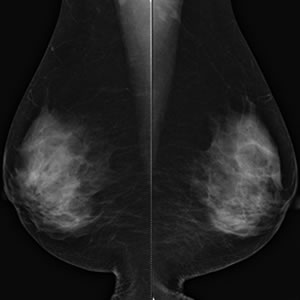

乳房のX線撮影のことです。乳腺内病変は正常乳腺と重なっていると発見が難しくなります。出来るだけ乳腺を分離させるため、専用の装置を使用し板状のプレートで乳房を挟んで圧迫し、薄く引き伸ばして撮影します。そのため、圧迫の際に痛みを生じますが、乳房の厚みを薄くすることで診断精度が高くなり尚且つ、患者様の被ばくを軽減するメリットがあります。

当院では50μm走査の高精細でマンモグラフィガイドラインの定める基準をクリアした撮影装置を使用し、日本乳がん検診精度管理中央機構の認定試験に合格した技師が撮影を行っています。

マンモグラフィ撮影画像